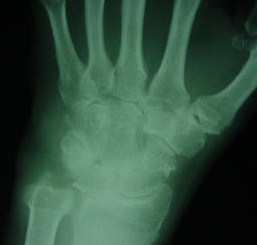

Q56) A 42 year old presents with a pain & swelling in the left knee. The symptoms started 3days ago and have been progressively worsening. Upon further questioning, the patient tells you that he has experienced intermittent pain and swelling in the toes, wrists and ankles for more than 10 years. On examination the left knee is swollen and warm to touch. There is also soft tissue swelling of the wrists, ankles and right foot. He has a 10 year history of intermittent pain & swelling in the toes, wrists & ankles. On examination the right knee is warm to touch with an effusion, & there is soft tissue swelling of the wrists, right ankle & right foot. X-ray of the wrist is shown below. Laboratory studies reveal increased ESR at 90mm/hr WBC are elevated at 12k.

The patient’s clinical presentation is consistent with acute flare of Rheumatoid arthritis. The x-ray reveals extra-articular erosion of ulnar styloid process. The involvement of proximal joints with accompanying soft tissue swelling, symmetrical involvement, history of chronic arthritis and extra-articular erosions on the x-ray are consistent with the diagnosis of Rheumatoid Arthritis. American Rheumatism Association (ARA) has developed 6 criteria for the diagnosis of RA. 4 out of this 6 criteria are necessary to diagnose RA. These include morning stiffness more than one hour, arthritis of 3 or more joint areas, arthritis of hand joints (wrist, MCP or PIP joint), Symmetric arthritis, Rheumatoid nodules, Serum rheumatoid factor

and Radiographic changes typical of rheumatoid arthritis on posteroanterior hand or wrist radiographs, which must include erosions within the involved joint or adjacent to the involved joints. This patient already has 4 out of six criteria for RA.

Ans. D is incorrect. Pseud-gout is usually acute mono-arthritis or oligoarthritis. It is very uncommon for pseudo-gout to present with polyarthritis. Pseudo-gout is also characterized by chondro-calcinosis which is deposition of calcium pyrophosphate crystals in the articular cartilage. Chondro-calcinosis can be visualized on the X-rays. The x-ray presented in the above case does not reveal chondrocalcinosis.